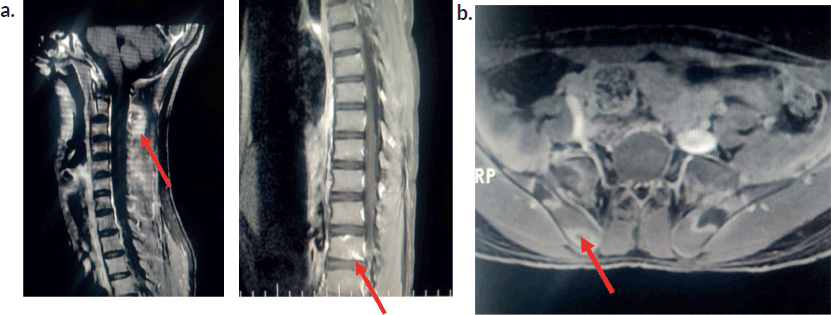

Initial investigations (Table 1) showed moderate anaemia, with normal total leucocyte counts, normal platelet counts and elevated inflammatory markers. His peripheral smear was normal with no atypical cells. The chest radiograph was normal. Ultrasonogram (USG) of the abdomen revealed mild splenomegaly and knee joint USG showed no evidence of synovitis or effusion. Work up for rheumatological conditions (Table 1) was negative. Due to persistent lowback pain and elevated inflammatory parameters, Magnetic resonance imaging (MRI) of the spine and pelvis was performed, which showed ill-defined T2 hyperintense lesions involving multiple cervical and thoracic vertebrae with Short Tau Inversion Recovery (STIR) hyperintense lesions in bilateral iliac bones and sacrum. There was an osteolytic lesion noticed in the spinous process of C2 with periosteal reaction . There was no leptomeningeal enhancement (Figure 2a and b).

Figure 2. Magnetic resonance imaging of the spine . (a): MRI spine-post contrast enhancement noted in C2 and C6 vertebral bodies.Osteolytic lesion noted at C2. Ill-defined enhancement noted in the paraspinal muscles posterior to C2 and thoracic vertebra. (b): MRI Hip -Ill-defined STIR hyperintense foci noted in bilateral iliac bones and sacrum (ala) with peripheral enhancement.